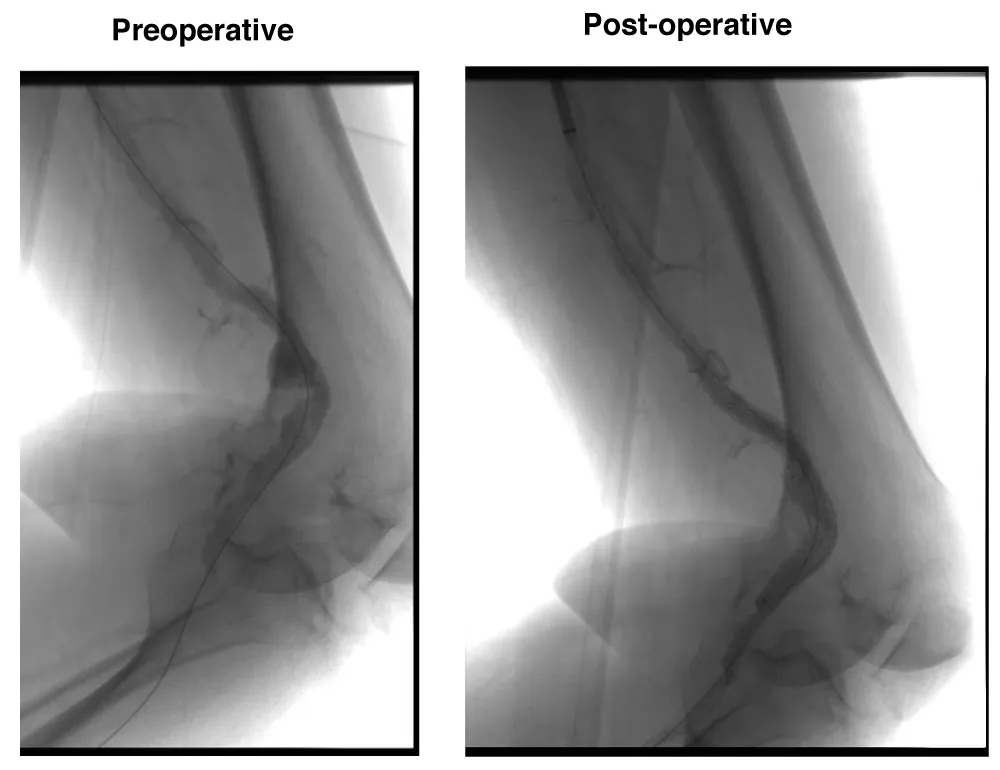

A male patient, 63 years, with arterial hypertension and dyslipidemia, was admitted with an asymptomatic popliteal artery aneurysm in the left Lower limb measuring 3,1 cm, discovered after an acute arterial occlusion at the right Lower limb due to popliteal artery aneurysm thrombosis. The following measures were observed: proximal neck diameter 10,21 mm, distal neck diameter 9,98 mm, with a diameter of 56 mm and 250 mm aneurysm length. The patient underwent endovascular treatment with the popliteal implant of endoprosthesis Wrapsody® 12x80 mm at the distal neck, followed by the implant of Wrapsody 12x125 mm and Wrapsody 12x80 mm at the proximal neck, followed by catheter balloon dilatation. The final image showed excellent results with no endoleaks (Figure 1). The patient was discharged from the hospital on the on the first postoperative day with Rivaroxaban 20 mg/day and a 6-month follow-up showed endoprosthesis patency with excellent flow and run-off.

Figure 1: Endovascular repair of a 63-year-old male with left popliteal artery aneurysm (56 mm): Preoperative imaging shows fusiform dilation of the popliteal artery. Postoperative image demonstrates successful deployment of three Wrapsody® endoprostheses (12×80 mm, 12×125 mm, and 12×80 mm) with complete exclusion of the aneurysm and no evidence of endoleak.